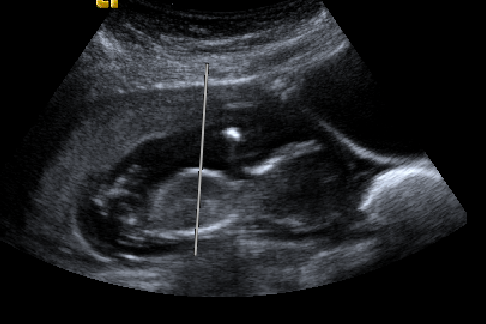

Would anyone like to take a guess at the gender? The attached photos were taken 13 weeks, 2 days. These are the best pics I have:

Attachment 25572Attachment 25573